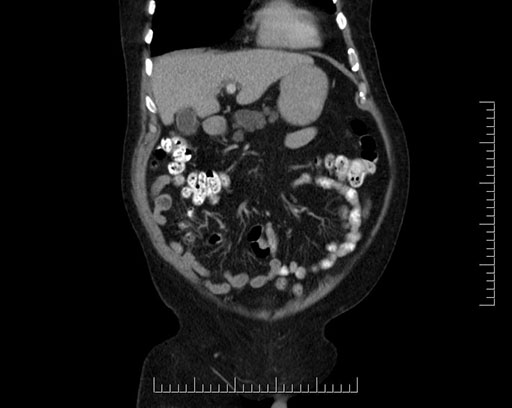

Coronal - stented